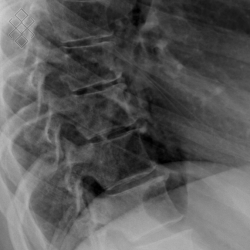

Radiographie du Rachis dorsal

Pour une radiographie du rachis dorsal, aucune préparation n'est requise. Il est recommandé d'enlever tous les bijoux avant de se présenter.

Vous serez installés en position debout.

La durée de l'examen est d'environ 5 minutes. Un ou plusieurs clichés radiographiques seront effectués. Le manipulateur vous positionnera en fonction de l'incidence radiologique à réaliser. Sauf indication contraire, il sera important de ne pas bouger durant la prise de clichés.

Avant de passer une radiographie du rachis dorsal, il est primordial de signaler si vous êtes ou pensez être enceinte. En effet, vous devrez passer l'examen sous certaines conditions.